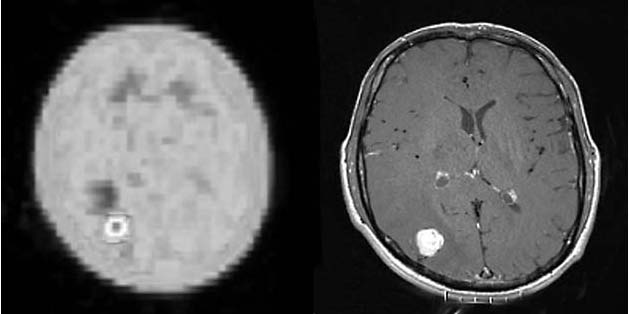

Obr. 2.

FLT - PET (obrázek vlevo) scan mozku s ložiskem zvýšené akumulace

radiofarmaka okcipitálně vpravo v korelaci s nálezem na MR (obrázek

vpravo). Metastáza sarkomu měkkých tkání stehna.